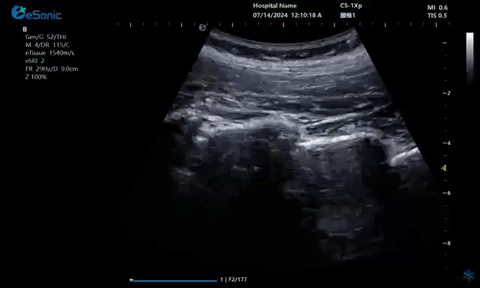

超声引导硬膜外麻醉-小等号

管内麻醉